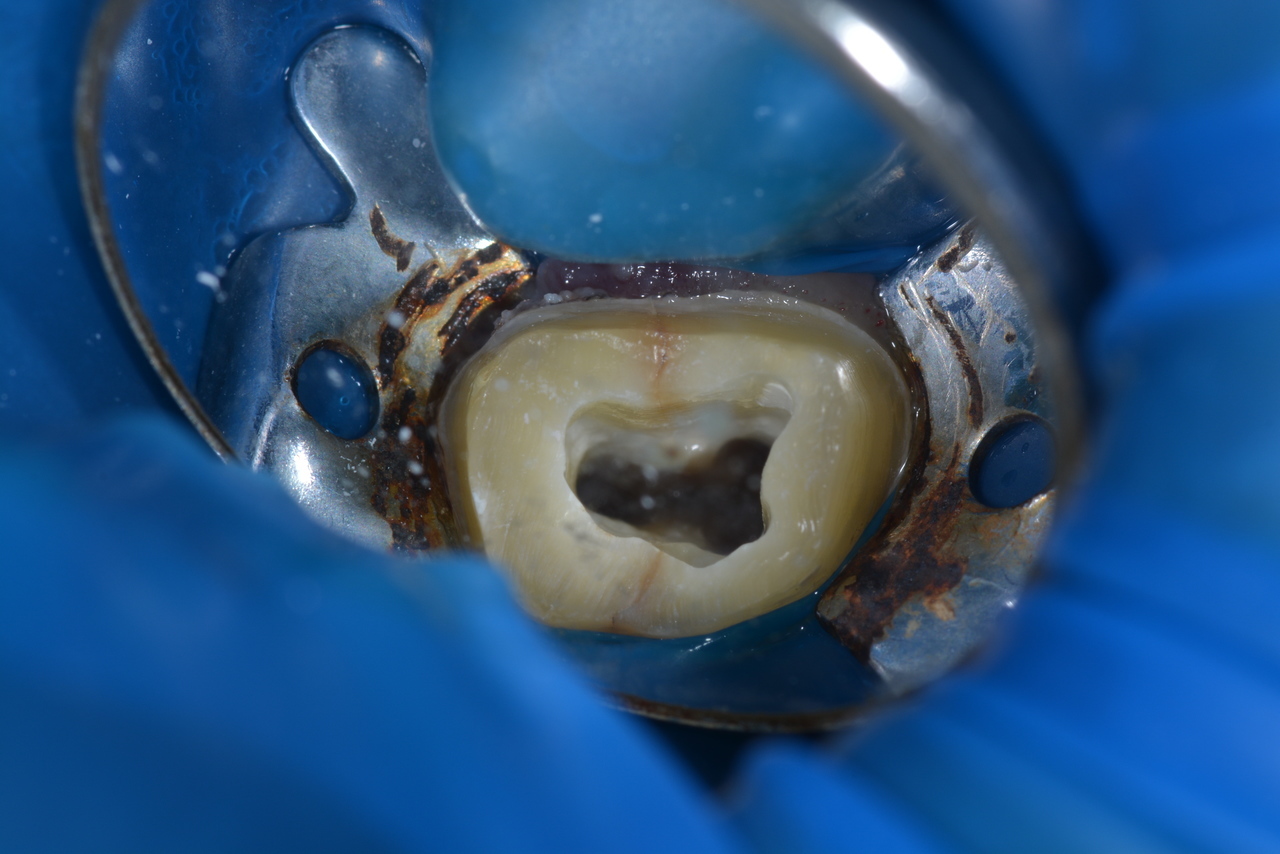

ラバーダムを使用した感染予防

当院では根の治療の際には「ラバーダム」を使用しています。ラバーダムとは、歯科治療の際にお口に装着するゴム製のシートのこと。治療する箇所以外をラバーダムで覆うことで、薬液や器具の誤飲を防ぎ、安全な治療を提供することができます。

また、シートが他の歯を覆うことで、唾液を介した細菌の進入を防ぎ、治療箇所の清潔を保つことができるため、新たな感染を起こすことのない安全性の高い治療が可能です。

そこで当院ではマイクロスコープ(顕微鏡)を使用し、複雑な根管の中を細部まで確認します。マイクロスコープを使えば、治療がされていない新たな根管を発見したり、肉眼では見えない細かな根の管を処置したり、歯の根のヒビや破切をきちんと確認できたりします。マイクロスコープを使うことで、痛みや違和感の原因をきちんと見極めた確実な治療を可能とし、根管治療の成功率を確実に上げ、結果的に歯の寿命を延ばします。